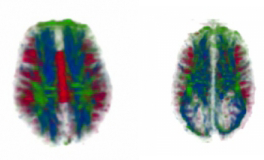

Left: diffusion tensor imaging for a typical brain. The large red area in the center is the corpus callosum. Right: brain of an individual with agenesis of the corpus callosum.